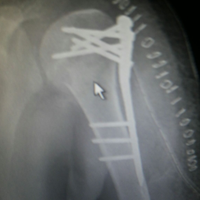

Case:7 Fracture Neck Femur with Implant failure and Re-Fixation with hemi-arthroplasty

Alcoholic Gardener by profession had slipped in bathroom & fell. He sustained fracture neck femur.He was operated with closed reduction & CC Screw fixation under IITV. Two weeks’ post fixation he again fell & sustained fracture in sub trochanteric region. He was treated with Hem-Arthroplasty with Tension band wiring.

Pre-Op

Post-Op

Post Fall